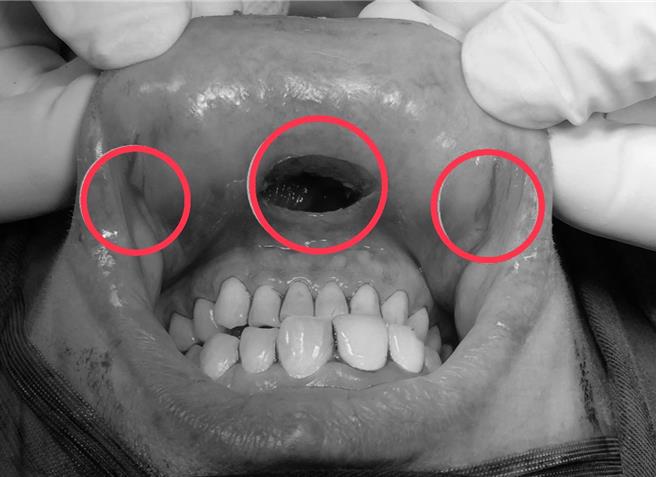

胡姓女大生日前體檢發現甲狀腺結節,以自然孔洞達文西甲狀腺手術進行切除,確認為惡性乳突狀甲狀腺癌,幸腫瘤小於1公分且無淋巴轉移,預後良好,也僅在口腔及臉頰內側有3處傷口。(仁愛長庚合作聯盟醫院提供/潘虹恩台中傳真)